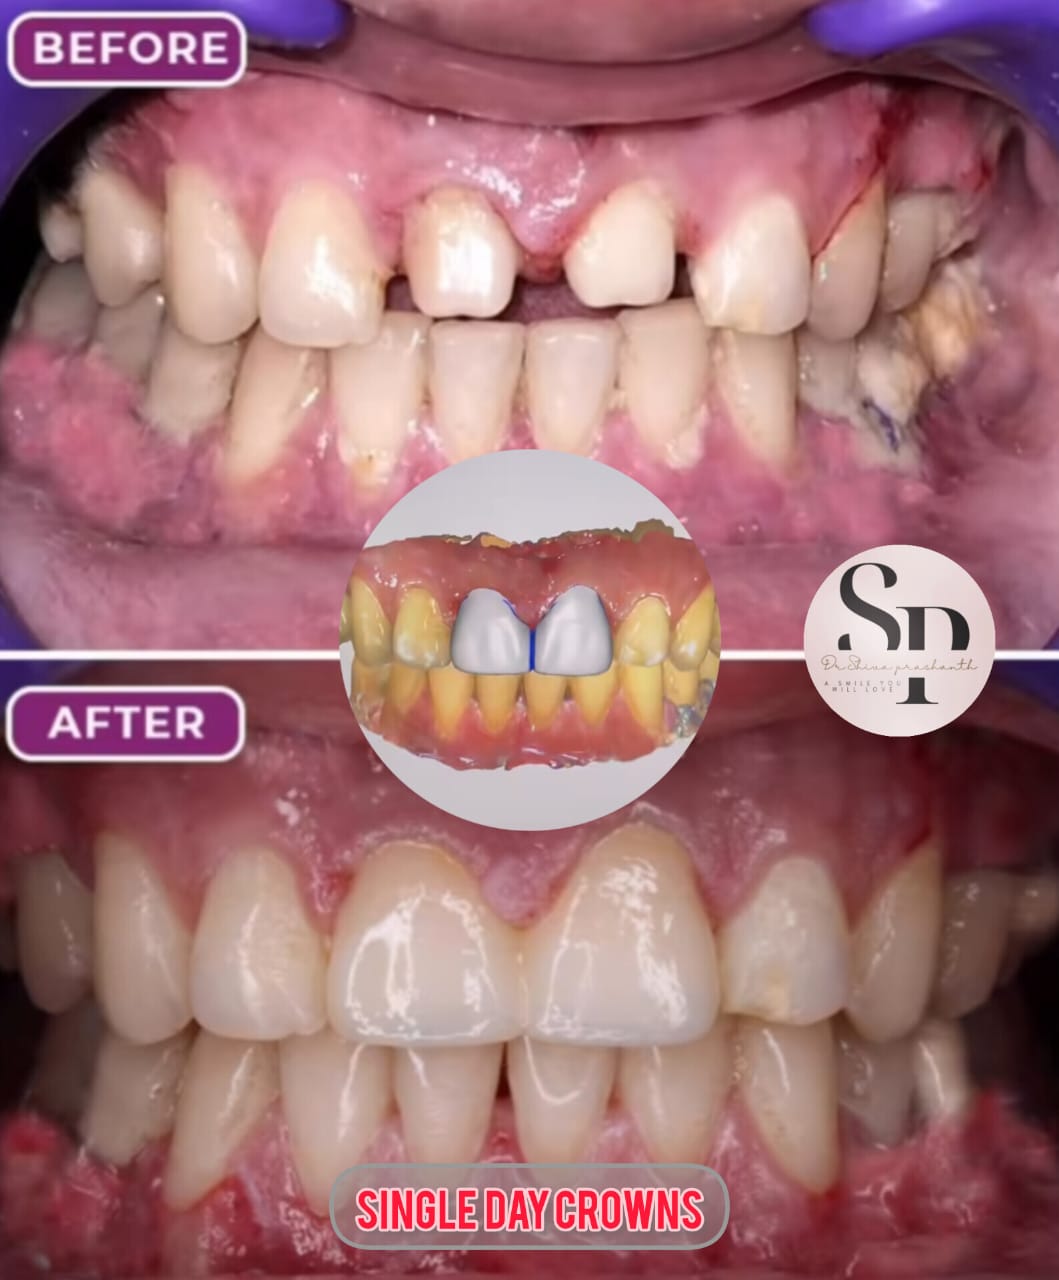

Smile Transformation Results

Real patient results showcasing confident, healthy, natural smiles.

Explore Our Care Moments

Discover insightful visuals highlighting smile transformations, advanced dental procedures, and patient care at our Hyderabad clinic.